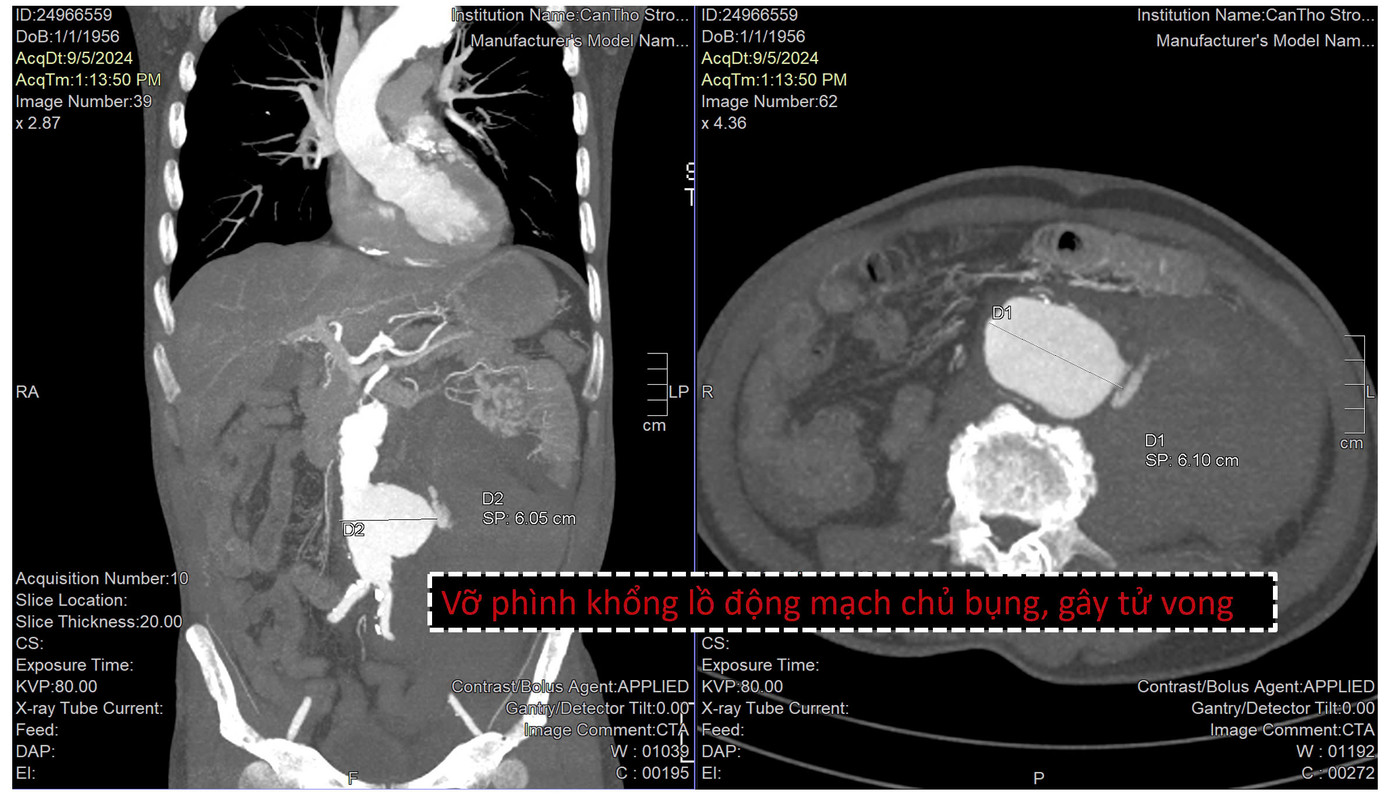

Trường hợp thứ nhất là nam bệnh nhân 58 tuổi được chuyển đến bệnh viện cấp cứu trong tình trạng mệt, đau bụng dữ dội. Qua siêu âm và kiểm tra hình ảnh, các bác sĩ phát hiện bệnh nhân bị phình động mạch chủ bụng, túi phình rất lớn hơn 6cm dọa vỡ.

Trước tình huống khẩn nguy của bệnh nhân, các bác sĩ đã nỗ lực triển khai biện pháp cấp cứu. Tuy nhiên, khi đang trong quá trình chuẩn bị can thiệp thì túi phình động mạch chủ bụng của bệnh nhân bị vỡ. Người bệnh rơi vào tình trạng mất máu cấp dẫn đến tử vong.

| Túi phình động mạch chủ bụng bị vỡ là nguyên nhân khiến người bệnh tử vong |